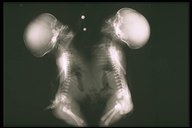

Thoracopagus Twins

In this thoracopagus twins, the thorax is joining from the manubrium to the xiphoid and uppar abdomen, a common umbilicus is noted

Humanogram showed separation heart shadow and fusion of sternum. A soft tissue shadow joining the upper abdomen indicated the fusion liver